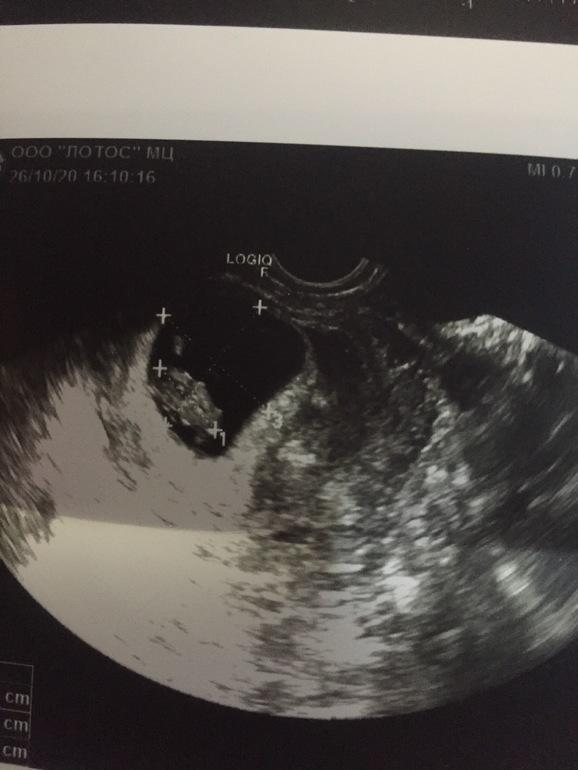

УЗИ 8-9нед

Девочки что то я не понимаю почему плохо видно карапуза?((( или по узи все нормально ?

Гематома только что. Но это заживает с грамотным лечением. На вашем сроке они у многих возникают.